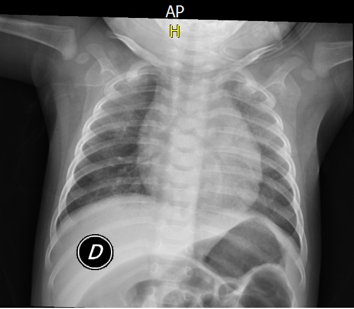

La noche previa a la consulta, según relata el padre de la paciente, se realizó dentro del hogar manipulación de “una bola de oro con fuego”, se presentó liberación de vapores en moderada cantidad, por lo cual suspendieron dicha actividad y encendieron el extractor de la cocina. La paciente se encontraba en otra habitación, a varios metros del lugar del incidente. Durante esa noche la paciente no presentó síntomas, la madre de la paciente refirió dificultad respiratoria transitoria que mejoró rápidamente. Aproximadamente 12 horas después de la exposición la paciente comienza a presentar cuadro de irritabilidad, disnea progresiva y tos; niegan fiebre u otros síntomas. Al ingreso a urgencias pediátricas se encontraba somnolienta, con síndrome de dificultad respiratoria, estridor, aleteo nasal, retracciones subcostales, sin hallazgos auscultatorios. Leve mejoría del estado neurológico después de administración de Oxígeno por cámara cefálica 98%, pero aún polipneica y con aleteo nasal, saturación 100%; radiografía de tórax con infiltrados intersticiales difusos y neumomediastino (Imagen 1).

Ante los hallazgos clínicos y de laboratorio se sospechó cuadro de neumonitis química asociada a inhalación de vapores de mercurio, dado el inicio súbito de los síntomas y dificultad respiratoria de rápida progresión; además madre de la paciente con síntomas respiratorios, aunque de menor intensidad.